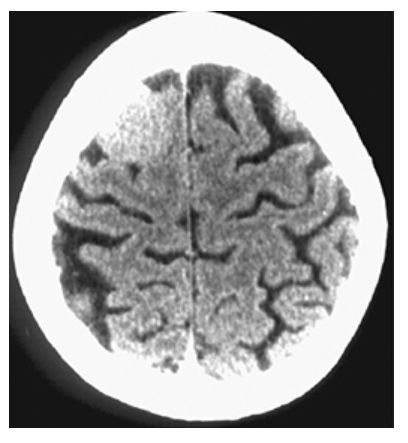

Agenesis of the Corpus Callosum. Axial CT and axial T1W MR

What is B

Agenesis of the Corpus Callosum. Axial CT show enlarged and parallel lateral ventricles with a “race car” configuration and no corpus callosum.